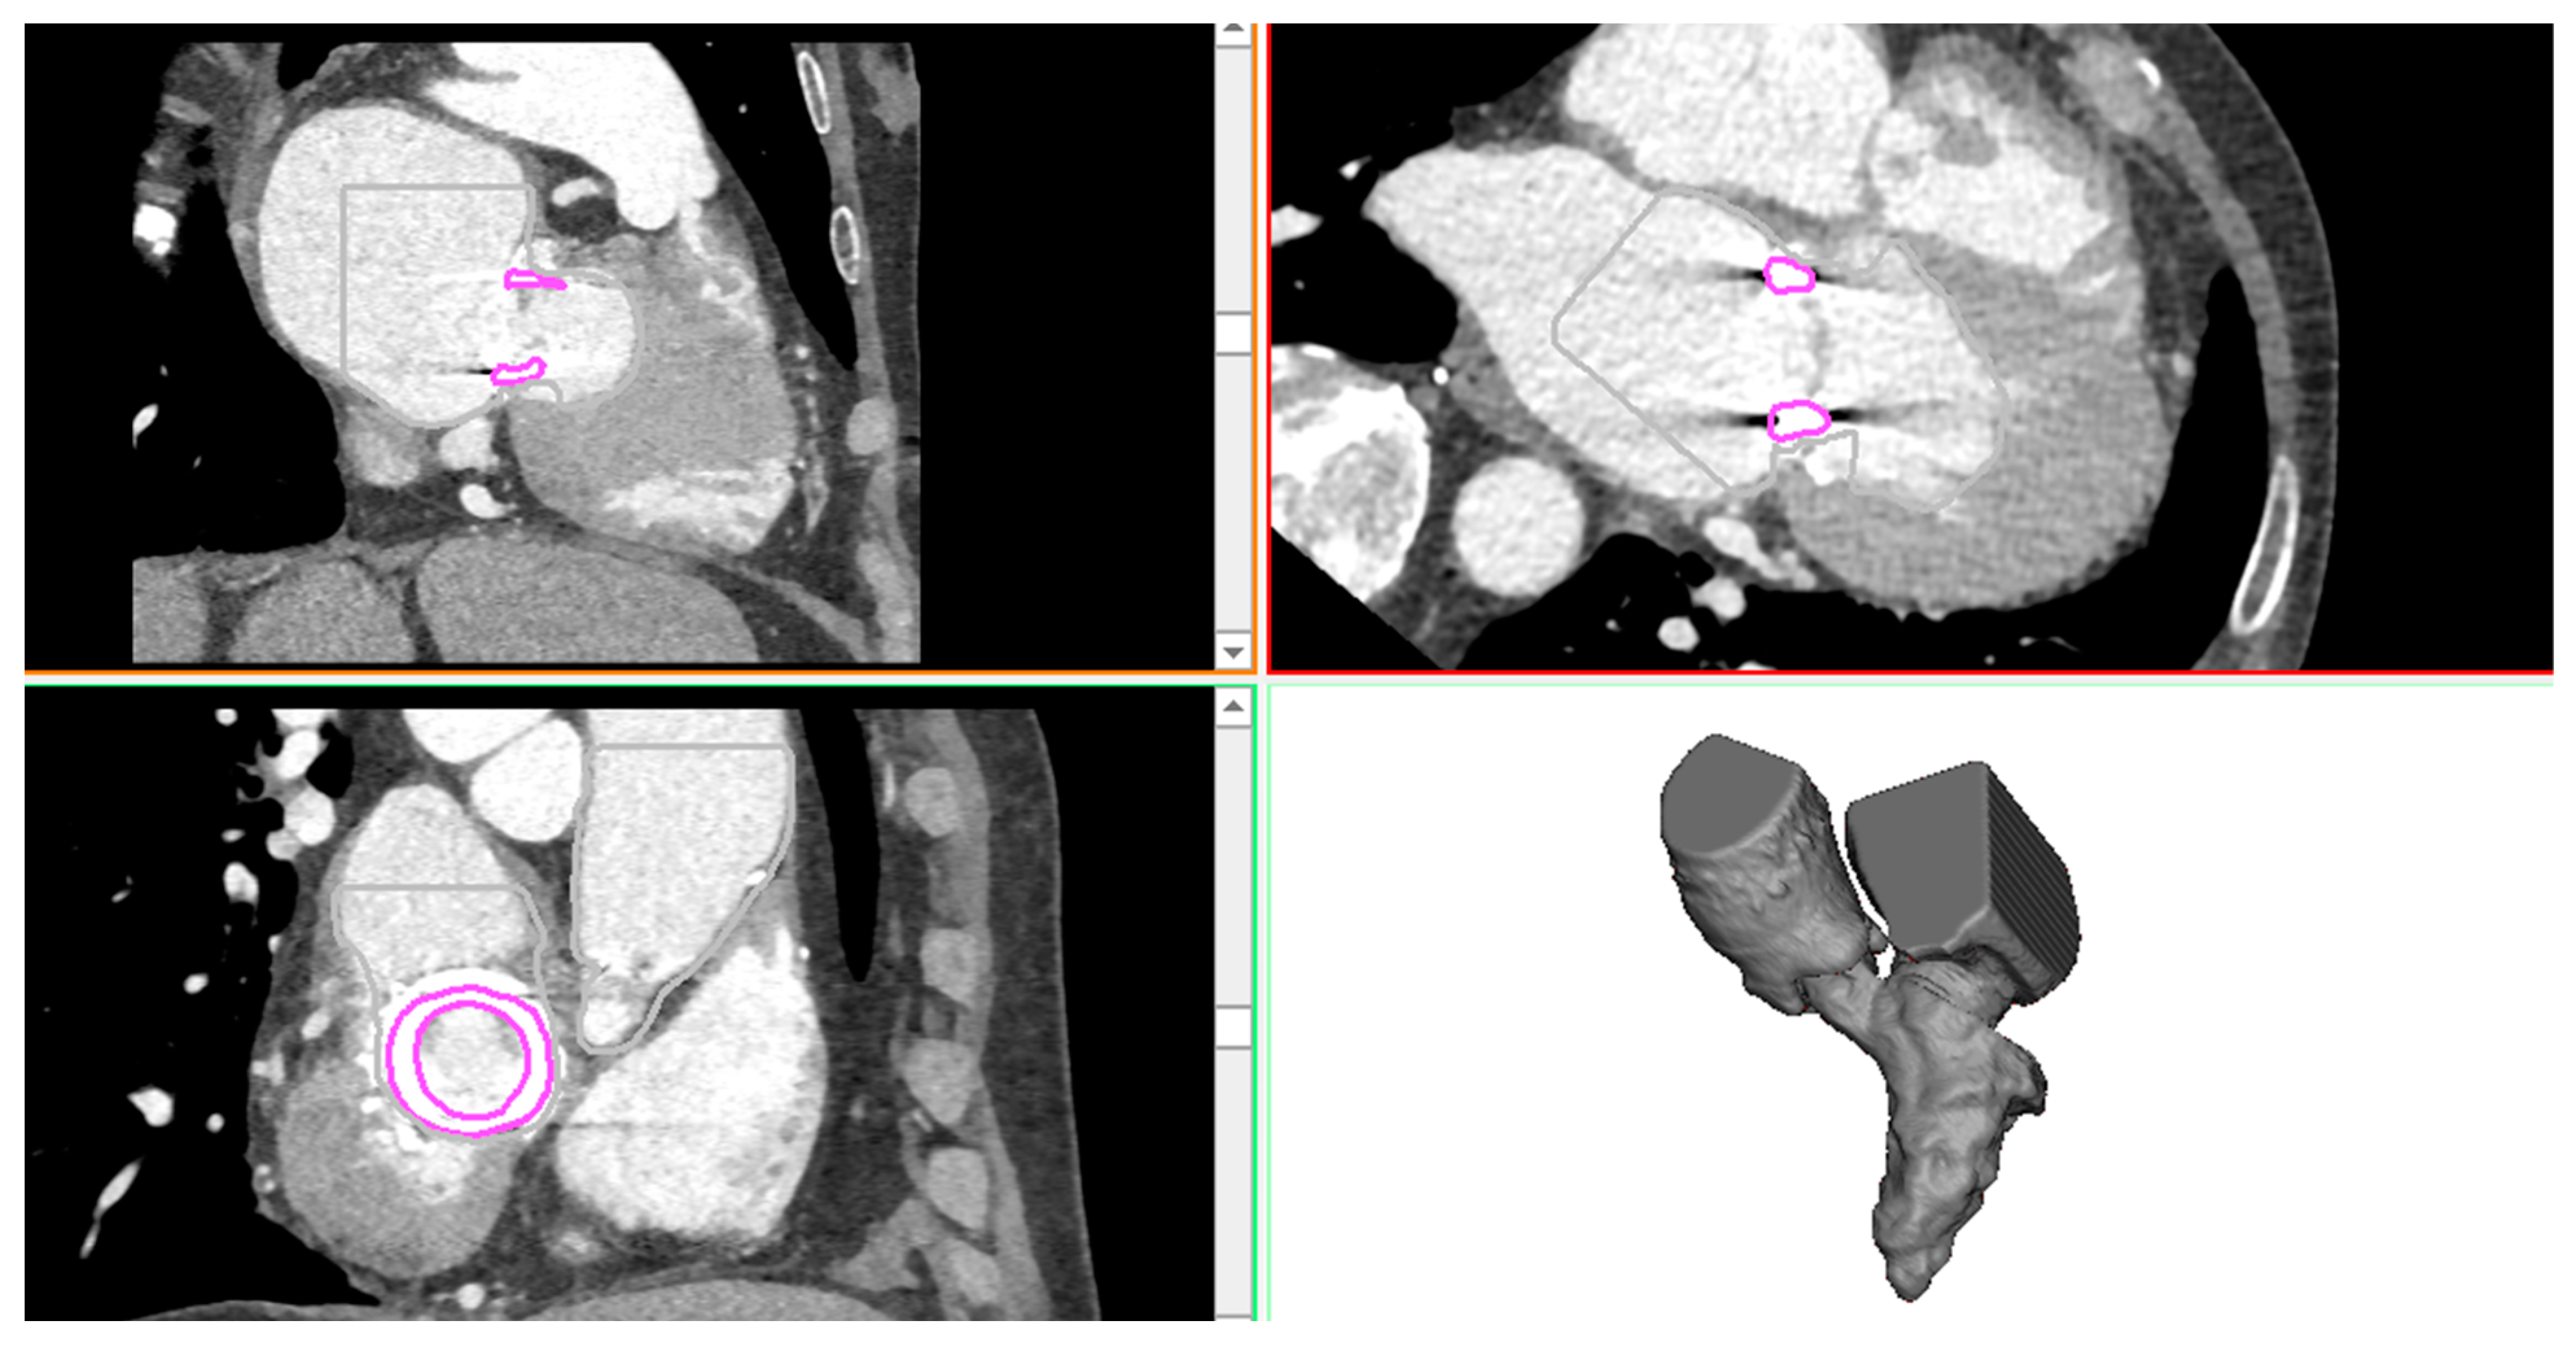

The patient case was a 74-year-old man presenting mitral valve failure of a previously treated bioprosthetic heart valve. CTA imaging was performed for this patient using a 64 detector-row CT scanner. Volumetric CT images in standard DICOM format were imported in Mimics to reconstruct the left ventricle, left atrium, and aortic root anatomy in terms of the spatial position and dimension by applying different gray values and multiple masks based on different Hounsfield unit thresholds. Segmentation was performed by semi-automatic thresholding operation followed by manual mask editing and morphological operation including cropping, erosion, and smoothing, as done previously by our group [14,15,16,17,18]. The bioprosthetic heart valve was distinctly reconstructed using a different mask. Figure 1 shows the heart anatomy as reconstructed from CTA images, while Figure 2 shows the reconstruction of the surgical bioprosthetic heart valve and annular dimension.

Figure 1.

CTA images showing the axial, sagittal, and coronal view as well as the 3D heart anatomy after segmentation.